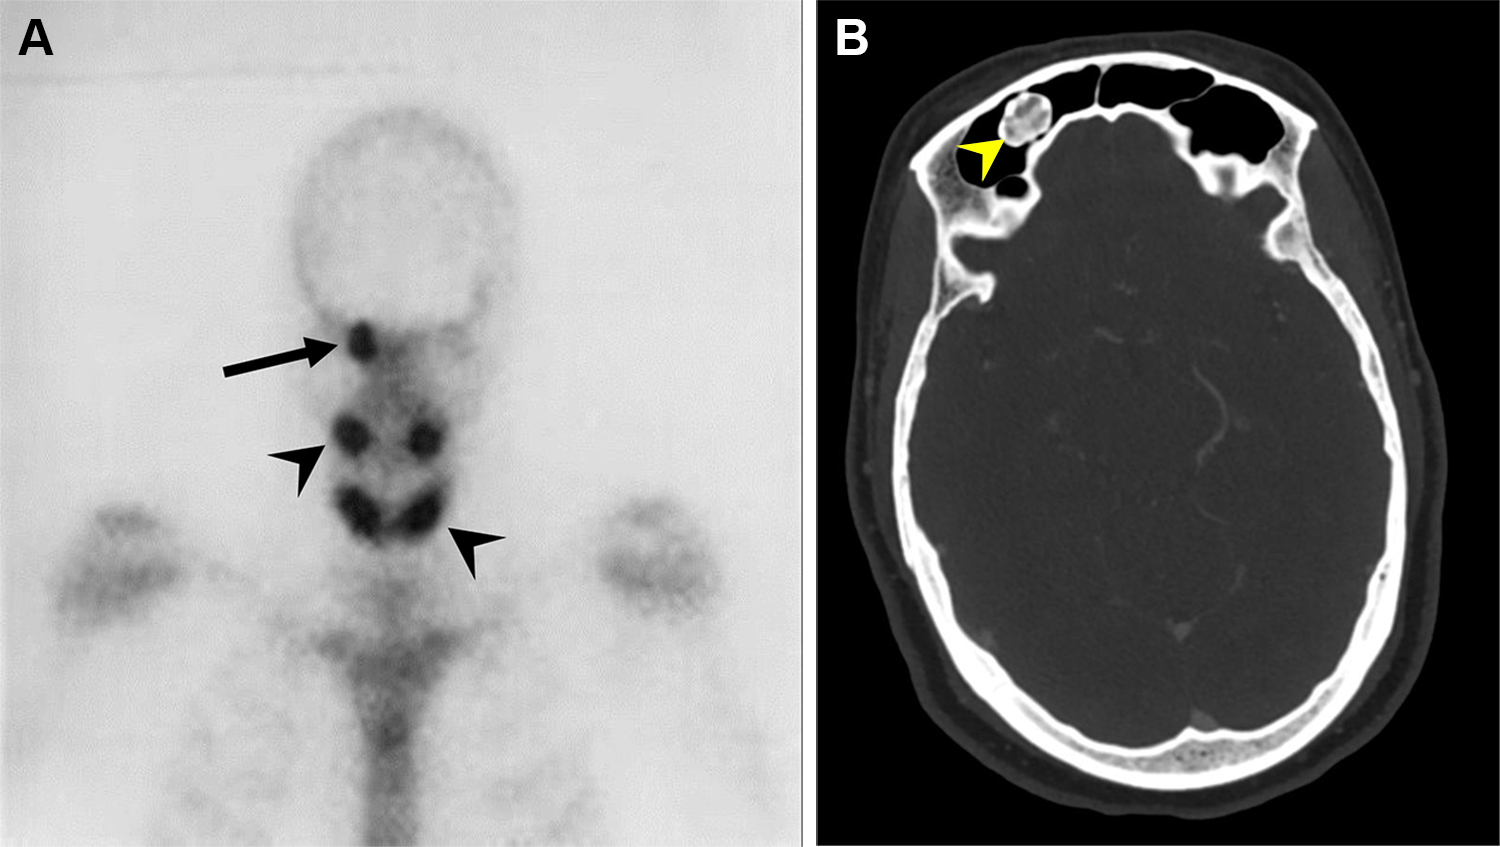

Giovane donna di 22 anni con massa frontale sinistra in lento e progressivo accrescimento da 8 anni. Presenta sintomi locali (arrossamento oculare, algie, cefalea) in assenza di deficit visivi. È stata eseguita una scintigrafia ossea con 99mTc-MDP.

Le immagini tardive (a) hanno mostrato una focale ed intensa captazione del tracciante nel cranio, in corrispondenza del margine sovraorbitario sinistro. Le immagini SPECT-TC nelle sezioni assiale (b), sagittale (c) e coronale (d) hanno evidenziato un’opacità a “vetro smerigliato” che coinvolgeva il margine posteriore del seno frontale sinistro, apparso ingrandito. La scintigrafia ossea ha documentato un quadro di displasia fibrosa monostotica.

Osteoma del seno frontale in un uomo di 69 anni con sindrome di Gardner.

Lo studio scintigrafico del distretto testa-collo evidenzia aree di intensa ipercaptazione focale (osso frontale destro, ossa mascellari e mandibola). Questo pattern è caratteristico per l’intensa attività osteoblastica tipica degli osteomi.

L’imaging morfologico TC conferma le aree di ipercaptazione come lesioni ossee estremamente dense e ben circoscritte (osteomi), localizzate in questo caso a livello del seno frontale destro.

La sindrome di Gardner è una variante fenotipica della Poliposi Adenomatosa Familiare (FAP). Si caratterizza per la triade clinica: polipi intestinali (ad altissimo rischio di trasformazione maligna), tumori ossei benigni (osteomi, quasi sempre cranio-facciali) e alterazioni dei tessuti molli (tumori desmoidi, cisti epidermiche). La scintigrafia ossea si rivela utile per mappare l’estensione delle manifestazioni scheletriche.